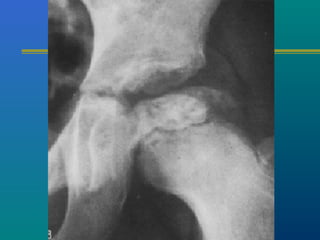

TB HIP- X-RAYTB HIP- X-RAY

 Osteoporosis

 Travelling acetabulum

 Dislocated hip

 Mortar and pestle appearance

 Perthes type

 Protrusio acetabuli

 Destruction of head